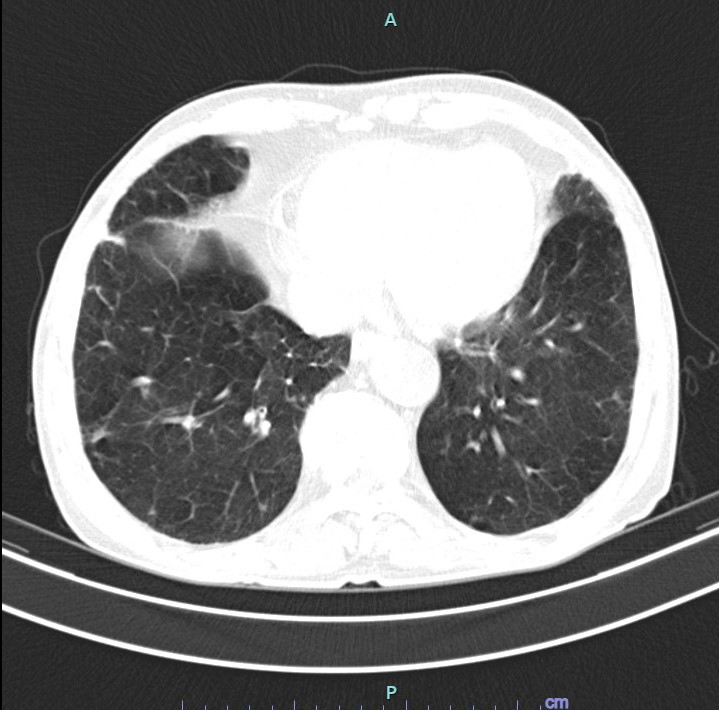

| Hình ảnh minh họa phổi của người không hút thuốc (trái) và của người hút thuốc (phải) |